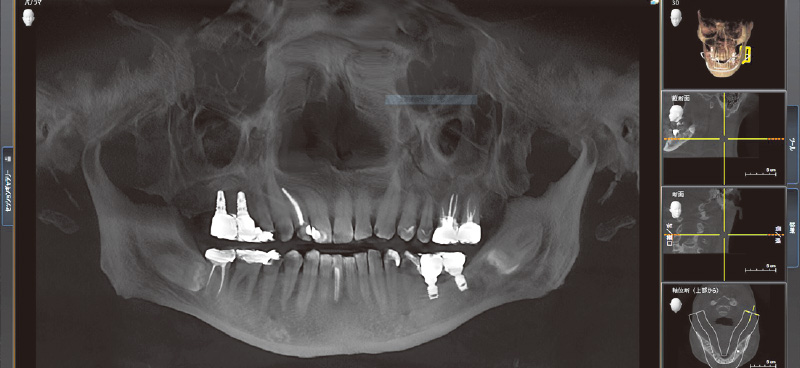

![[写真] CT画像よりサイナスリフト後、インプラント埋入を行うに十分な骨量が確保されている状態を確認できる](/academic/dentalmagazine/wp-content/uploads/sites/2/2025/11/195-10_photo03.jpg)

図3 CT画像よりサイナスリフト後、インプラント埋入を行うに十分な骨量が確保されている状態を確認できる。SPIインプラントシステムの特徴的なドリルは、シンプルで正確な埋入手術を可能としている。(デンツプライシロナ社製CTにて撮影) -